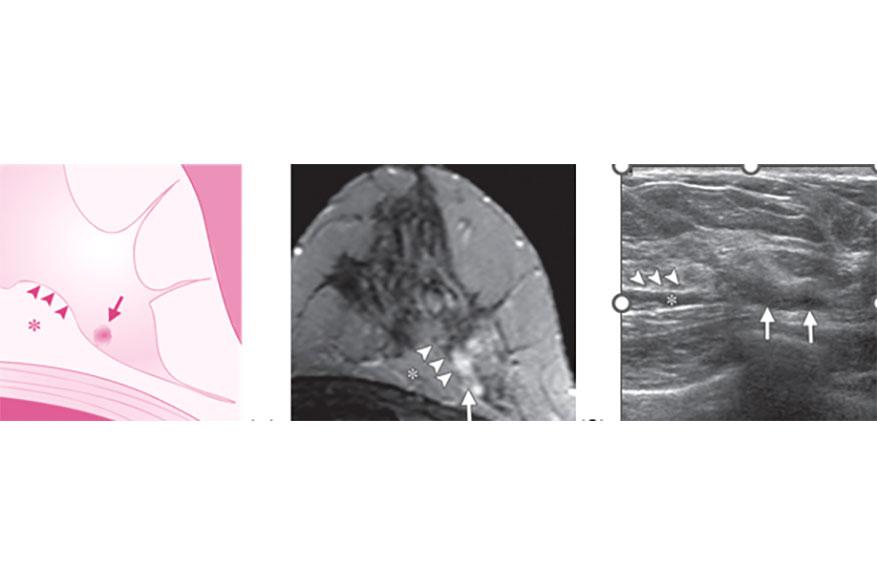

ΣΤΟΧΕΥΜΕΝΟ ΥΠΕΡΗΧΟΓΡΑΦΗΜΑ ΜΑΣΤΩΝ -second look us - (SLUS)

Η μαγνητική τομογραφία (MRI) χάρη στην υψηλή ευαισθησία, αναγνωρίζει βλάβες που δεν είχαν προηγουμένως ανιχνευτεί με συμβατική απεικόνιση, δηλαδή με μαστογραφία και /ή υπέρηχο και λέγονται τυχαίες ή επιπρόσθετες MR-αλλοιώσεις.

- Για όλες αυτές τις αλλοιώσεις του μαστού, είναι απαραίτητη μια δεύτερη ματιά με USσύμφωνα με τη βιβλιογραφία.

Ο ρόλος του στοχευόμενου υπερηχογραφήματος (SLUS) για τις MRI-αλλοιώσεις που έχουν αναδειχτεί με μαγνητική τομογραφία είναι μια στοχευόμενη επανεκτίμηση του μαστού με υπερήχους (US) για την ανάδειξη των τυχαίων ή επιπρόσθετων ανιχνευόμενων από τη μαγνητική τομογραφία βλαβών που δεν είχαν προηγουμένως αναγνωριστεί με άλλες μεθόδους απεικόνισης και να ακολουθήσει βιοψία καθοδηγούμενη από US για ιστολογική ταυτοποίηση.